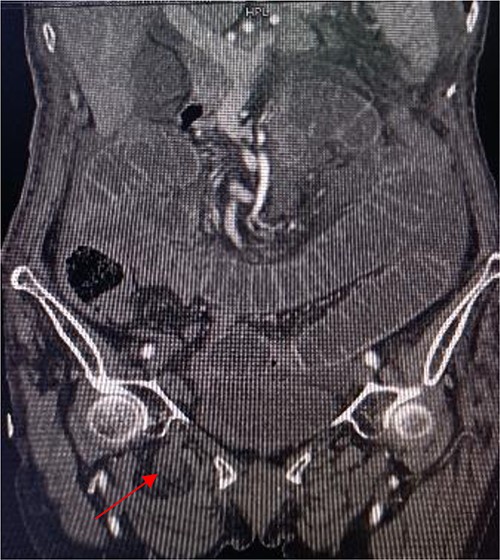

An 86-year-old female complained of constipation with abdominal pain, nausea, and vomiting for ˃2 weeks. The patient had defecated once, after conservative treatment with an enema in a local hospital, with less abdominal pain and no nausea or vomiting; hence, she was admitted to our hospital for further diagnosis and treatment. The patient’s body temperature was 36.8°C, pulse rate was 87 beats/min, respiration rate was 18 breaths/min, and blood pressure was 125/76 mmHg. The patient was conscious and had a thin appearance, and physical examination indicated that the abdomen was soft, and without tenderness and rebound pain. Routine blood examination showed that hemoglobin was 87 g/L and hematocrit was 28.3%. Abdominal computed tomography revealed the right lower abdominal small intestine protruding into the femoral triangle through the obturator; the upstream intestine was distended and expanded, and multiple fluid levels were observed in the intestinal lumen. Multiple lymph nodes were noticed in the abdomen and retroperitoneum; the large ones had a diameter of ~1 cm. Uneven thickening and enhancement of the local ascending colon were noted.

Computed tomography axis map showing the small intestine entering the femoral triangle (red arrow).